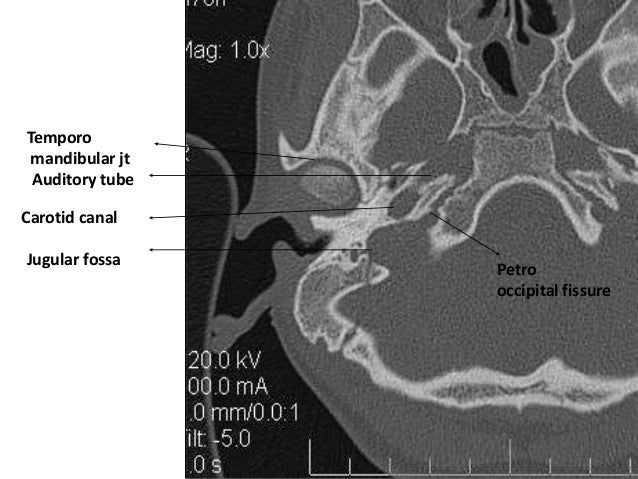

Radiologic Anatomy Of The Temporal Bone | Radiology Key

Temporal Bone | Radiology Key

Temporal bone. Temporal bone cross section. Petrous bone anatomy